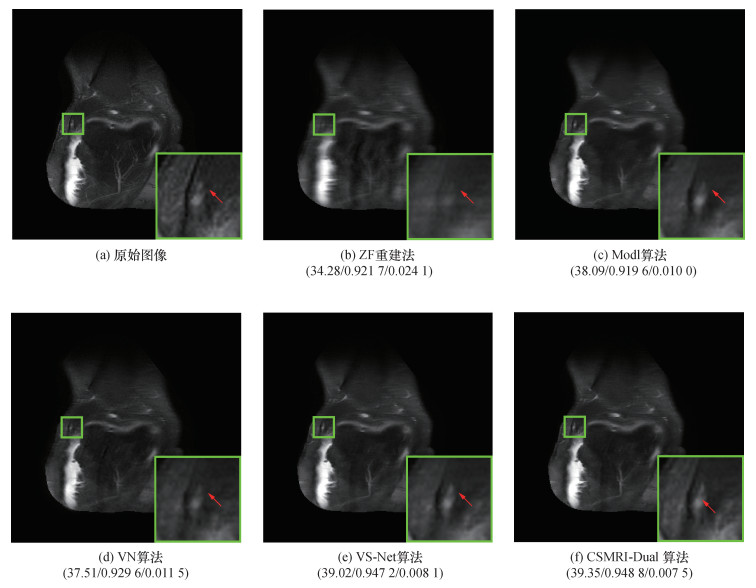

为进一步评估本文提出的CSMRI-Dual算法的重建效果,图 2和图 3分别展示了在4倍和6倍AF时,不同算法重建图像的区域放大图。由图可知,ZF重建图像非常模糊,并且图像过于平滑,缺少细节信息;Modl算法恢复出的重建图像同样丢失了很多的细节信息;VN算法和VS-Net算法重建图像类似,比Modl算法恢复出的重建图像有明显提升,但是细节信息依旧有部分丢失;CSMRI-Dual算法重建图像在4倍AF下视觉效果较好,有效消除了噪声,获得了更多细节,且保留了丰富的纹理信息;在6倍AF下,重建细节更接近原始图像,重建图像较为清晰。由此可见,CSMRI-Dual算法表现出了良好的重建效果。

| 图 3 6倍AF下不同算法重建图像的对比(平均PSNR/SSIM/NMSE) |